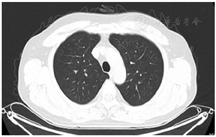

2021年7月15日复查胸部CT显示肺部感染吸收好转(图2、图3),遂停用糖皮质激素,抗生素降阶梯为头孢曲松(2 g,静脉滴注,1次/d)。BALF mNGS回报后检索惠普尔养障体感染有关文献的治疗方法亦首选头孢曲松,故继续予以头孢曲松治疗,头孢曲松治疗1周后患者病情平稳出院。院外继续长期口服甲氧苄啶磺胺甲唑(0.96 g,2次/d)治疗,停用糖皮质激素,3个月随访时患者自诉视力下降、慢性腹泻、多关节痛均得到缓解,生活质量提高。2022年3月复查胸部CT右肺上叶肺炎吸收(图4)。目前患者仍在接受口服甲氧苄啶磺胺甲唑(0.96 g,2次/d)的治疗,继续随访。